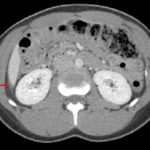

- Moderate volume free fluid layering in the pelvis and small volume perihepatic ascites

Findings concerning for bilateral pyosalpinx and possible right tubo-ovarian abscess. Small volume perihepatic fluid could relate to associated perihepatitis (Fitz-Hugh-Curtis syndrome).